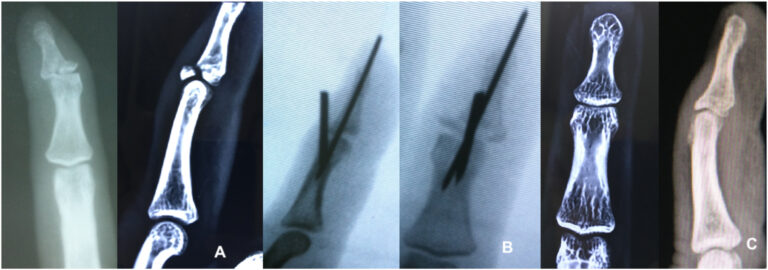

La colocación de clavos en bloque de extensión percutánea es una de las modalidades de tratamiento para las lesiones óseas desplazadas en martillo. Se han descrito varias modificaciones técnicas con una o más agujas de Kirschner. El propósito de este estudio es analizar los resultados de la fijación con alambre de Kirschner dorsal específico de un fragmento para las fracturas en martillo.

- Sugerimos la primera aguja de Kirschner como paso clave para la reducción de fragmentos de fracturas.

- Aguja de Kirschner de lados radiales para desplazamiento dorso-radial.

- Un lado cubital para el desplazamiento dorso-cubital.

- Dos agujas de Kirschner dorsales paralelas para el fragmento central.